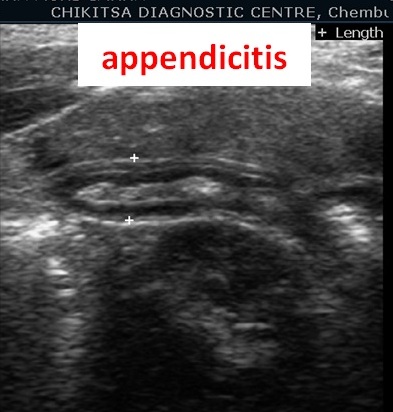

Abdominal ultrasound is used to check the major organs in the abdomen including the liver, gallbladder, kidneys, pancreas, spleen and urinary bladder.

Many pathologies can be detected , such as gallstones, kidney stones, appendicitis, enlargement of organs (such as liver, spleen, or kidneys), pancreatitis, cancers in the abdomen, hernias, fluid in the abdominal cavity, abdominal aortic aneurysms etc.